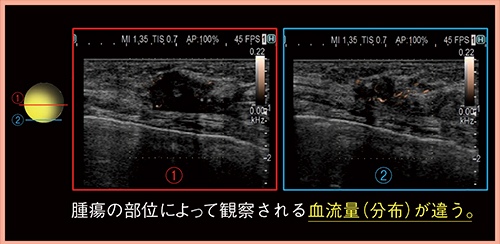

DFIでは,腫瘍中心よりも辺縁から多くの血流を受けており,部位によって観察される血流量(分布)が異なることがわかる(図1)。また,Bモードだけでも悪性と判断できるが,RTEも悪性を支持する所見であった(図2)。RTEでは,脂肪と病変のひずみの比であるFat Lesion Ratio(FLR)(図2□)がワンタッチで自動計測でき,非常に簡便である。FLRは数値が大きいほど腫瘍が硬いことを示すが,この腫瘍は中心が9.64,辺縁が15.08と部位によって硬さが異なっていた。針生検の結果も,部位によって細胞成分や線維(間質)の分布が不均一であることから,DFIやRTEの差は組織構築成分の違いを見ているものと考えられる。DFIとRTEを組み合わせることで,より的確な生検部位の同定が可能になると思われる。

図1 症例1:腫瘍の部位によるDFIの比較